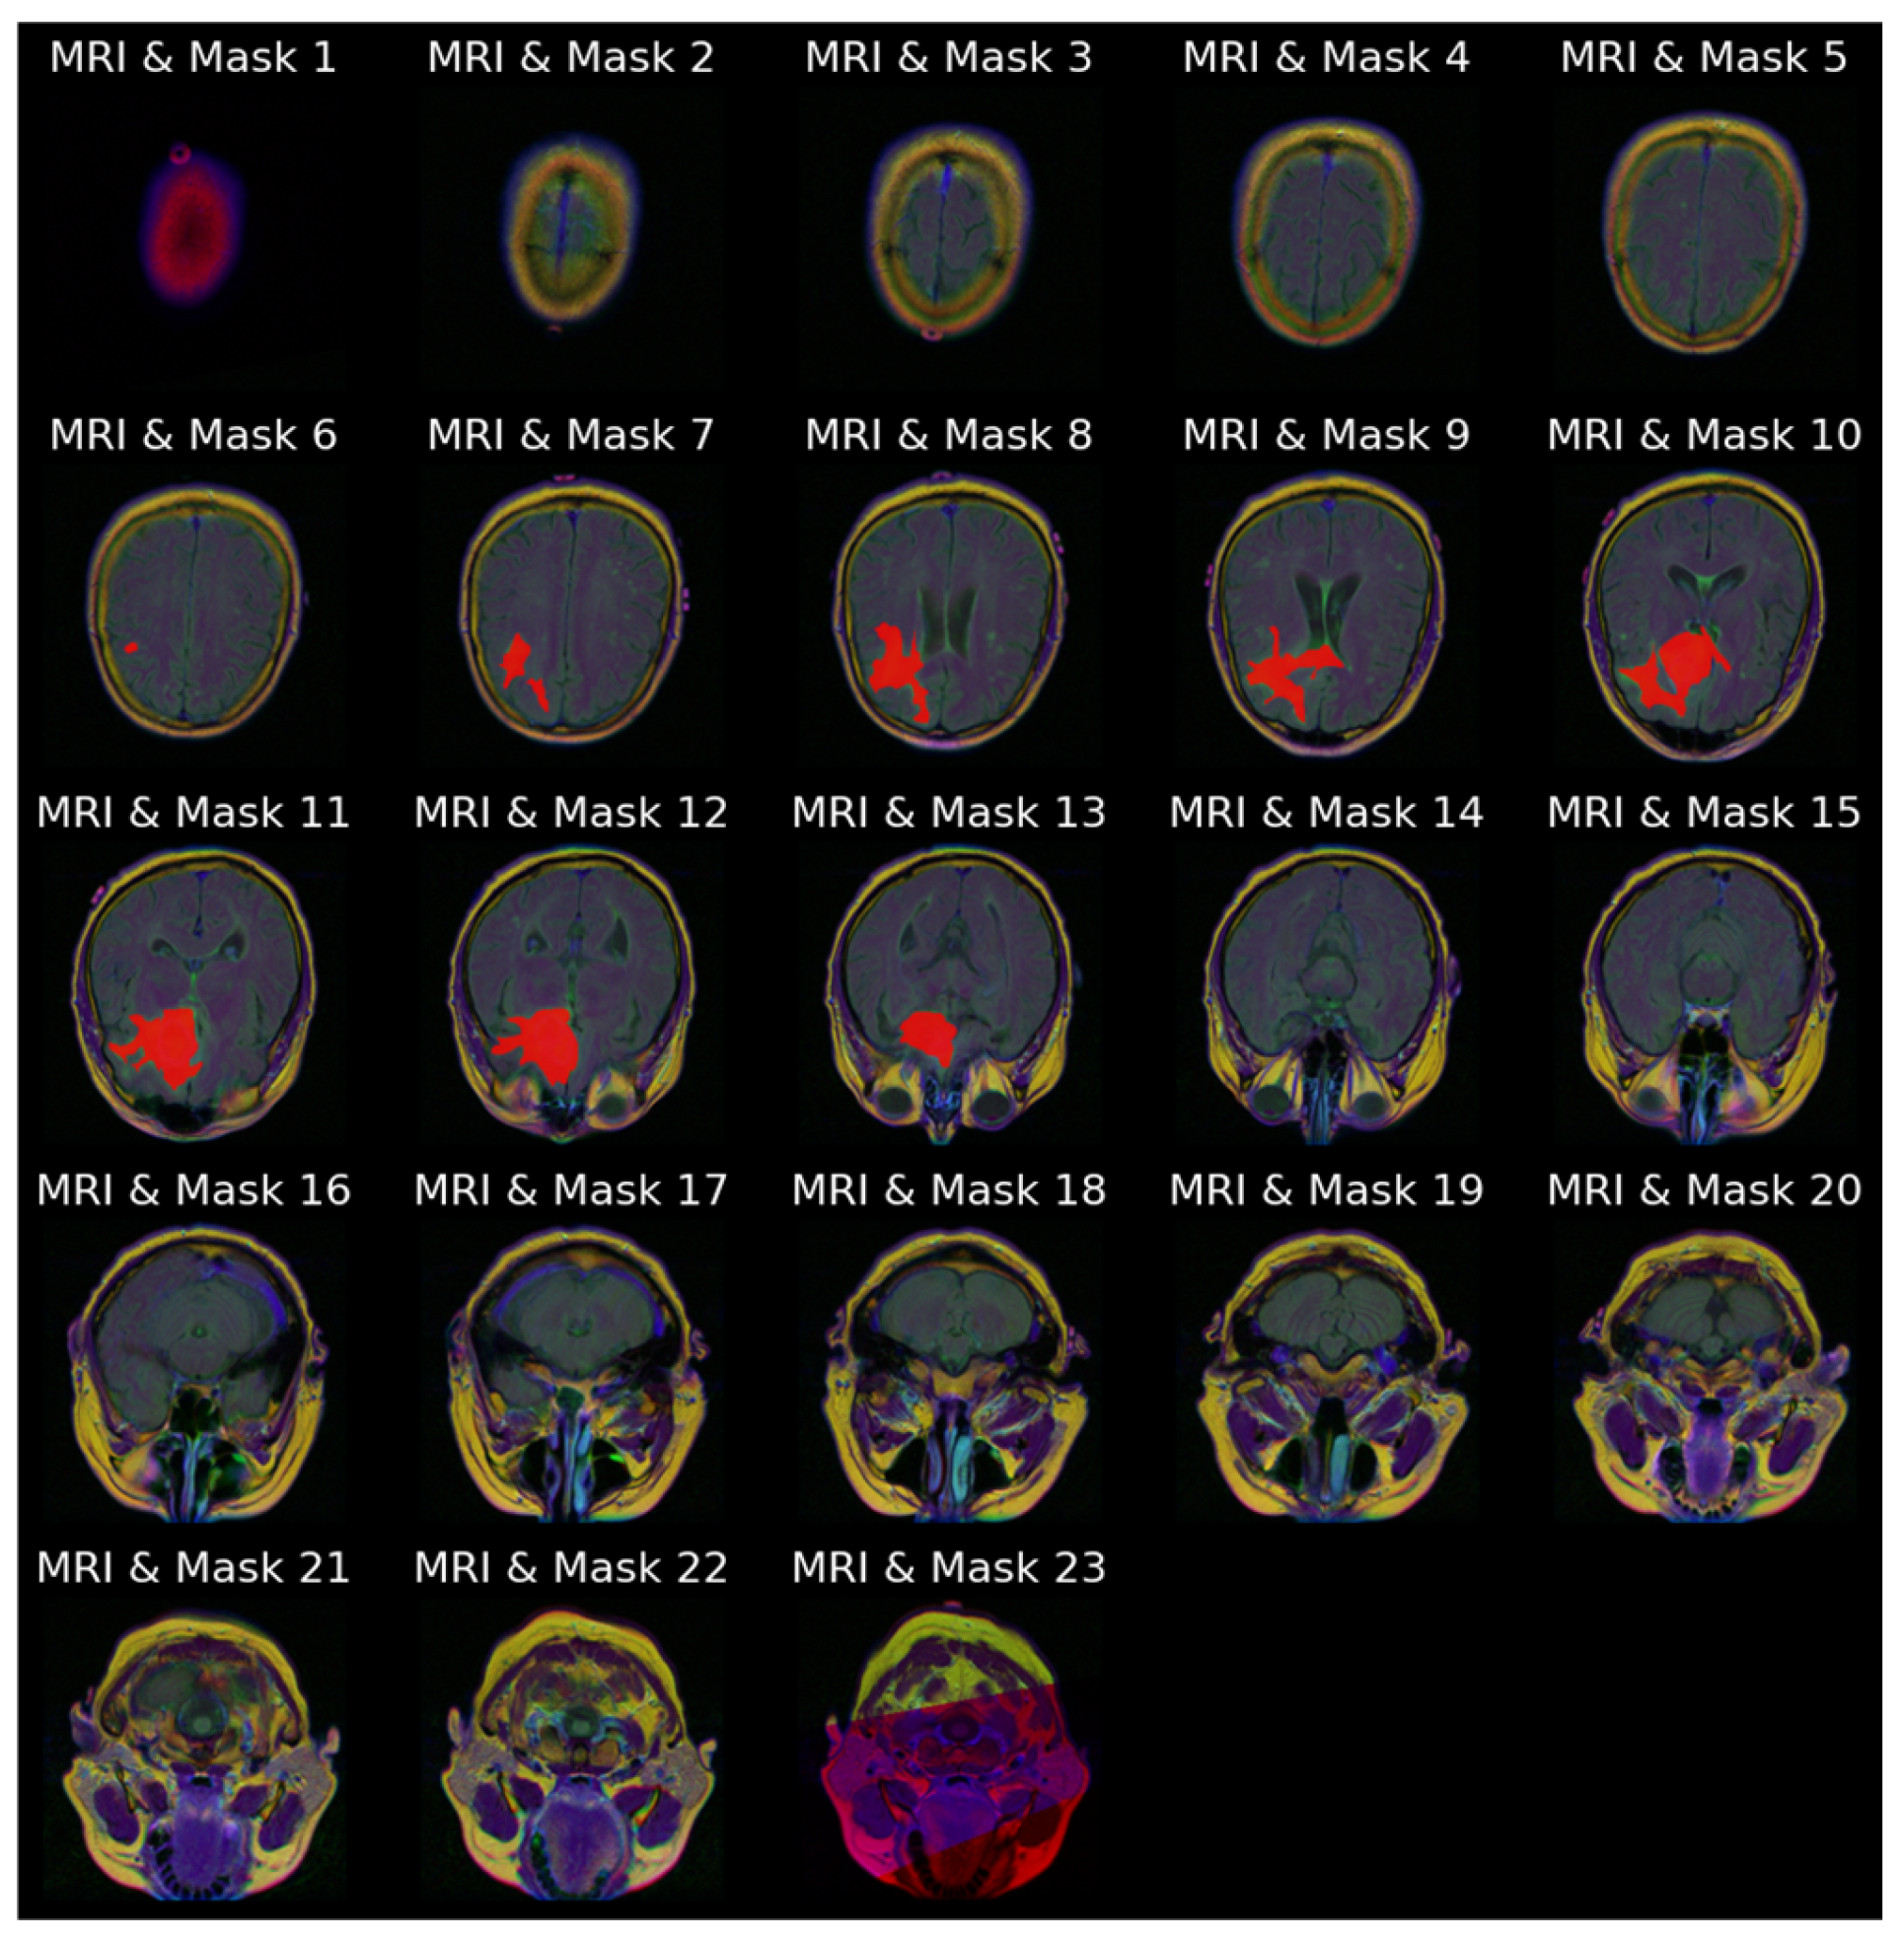

Figure 4a stacks all 23 slices available for the same patient in cranio-caudal order. The sequence reveals how the cranial vault initially appears tumor-free and gradually opens to reveal the lesion, which then enlarges before disappearing again. Figure 4b presents the ground truth masks for those 23 slices without the underlying MRI signal, emphasizing the sparsity of positive pixels in many frames.

Figure 4.

Anatomical order visualization for patient with ID “TCGA_CS_4941_19960909”: (a) Complete set of 23 axial FLAIR slices; (b) ground truth tumor masks.

Figure 5 combines the two views of Figure 4, overlaying every mask on its corresponding MRI slice-image, reinforcing the spatial coherence of the annotations that will later be used as a qualitative benchmark for model outputs.

Figure 5.

Image–mask (red) overlays for all 23 slices for patient with ID “TCGA_CS_4941_19960909”.